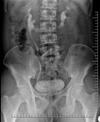

Horseshoe Kidney

Case courtesy of Dr Aditya Shetty, Radiopaedia.org. From the case rID: 27958